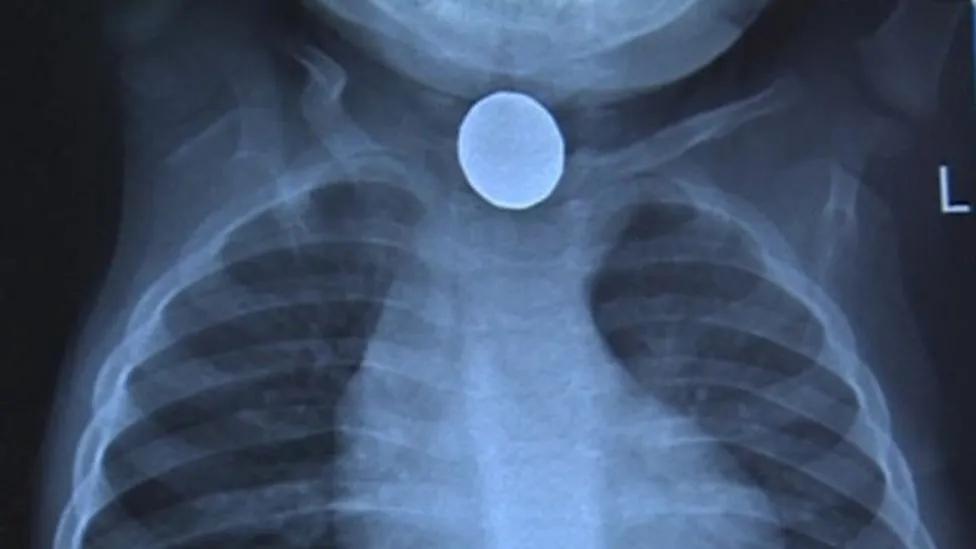

原来,一颗小小的纽扣电池,死死地卡在了休伊的食道里,导致他的心脏烧出了一个硬币大小的洞,并且他的其他内脏也出现了不同程度的损伤,尤其是肺部衰竭十分严重。

这主要和食道里的黏膜有关。我们的食道里充满了粘膜,纽扣电池在被吞入体内后,一旦被黏膜夹住,就会形成一个传导路,导致电池瞬间短路。我们知道,在家里电器短路就会发热甚至着火,而电池短路也会发热造成黏膜烧伤,甚至烧穿食道和气管造成穿孔。